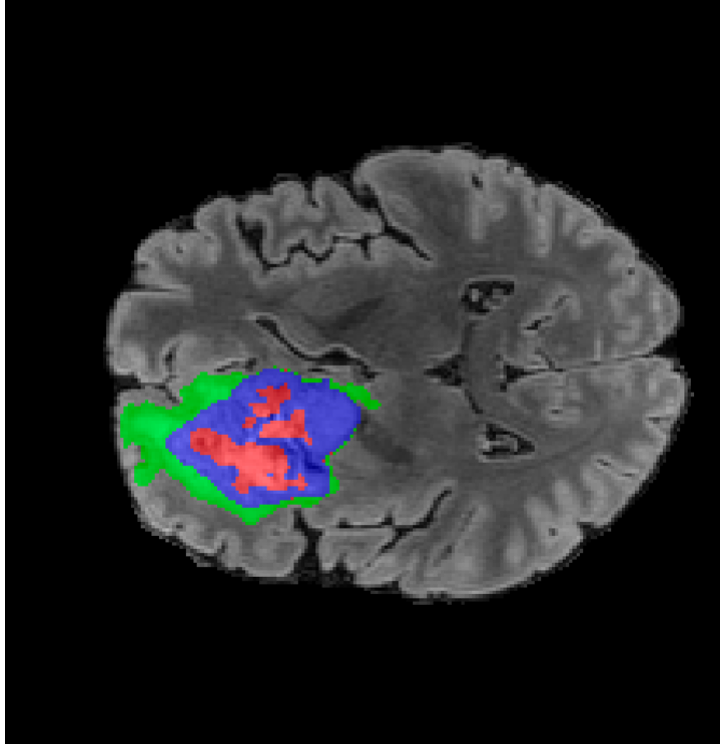

Tumour Information Preservation. For the brain tumor segmentation, we use a Swin UNETR model[28, 70], trained with random rotation, and intensity as data augmentation. On the test set with human ground-truth annotations (), the brain volumes generated from single slice input preserve the volume of the different tumour components (paired t-test, for all 3 classes). In Figure 4, we highlight the tumor profiles of the generated MRIs compared to the ground truth tumour profile. The real MRI Dice score in the test set is 85.15 while the generated MRIs from a single slice have a dice score of 83.09. This shows how the generated MRIs indeed preserve the tumor information and can act as an affordable and informative pseudo-MRI, before conducting an actual costly MRI examination in hospitals. More detailed results are provided in supplementary material.

On the test set with human ground-truth annotations (), the brain volumes generated from single slice input preserve the volume of the different tumour components (paired t-test, for all 3 classes) (see Table I). The real MRI Dice scores are put for reference to our generated MRIs. X-Diffusion outperforms baselines TPDM [39] and ScoreMRI [19] in tumour preservation (see Table I and Figure III). We ran experiments comparing the tumour segmentation Dice Score varying X-Diffusion configurations. The multi-slice input X-Diffusion achieves marginally better Dice Score than the single slice input model (83.47 83.09). We also ran experiments with slice input used for volume reconstruction intersecting or not with tumour. We observe on average a drop of 6% Dice Score (see Table I). Further away from the tumour the input slice for volume reconstruction is selected, we observe a linear decrease in tumour segmentation Dice Score with lowest value of 77.21 Dice Score (see Figure VI).